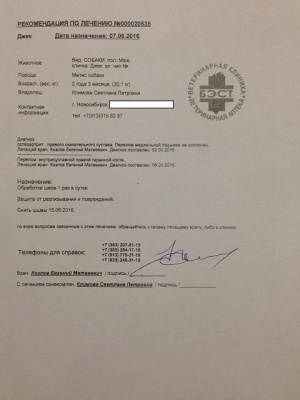

– предоплата за проведение компьютерной томографии правого скакательного сустава (КТ) врач Горшков Сергей Сергеевич, и операции (снятие пластины) хирург Козлов Евгений Матвеевич, клиника Бэст (чек 1, заключение КТ – документ 1, лист назначений – документ 1-1) – 5000 руб.;

– предоплата за проведение компьютерной томографии правого скакательного сустава (КТ) врач Горшков Сергей Сергеевич, и операции (снятие пластины) хирург Козлов Евгений Матвеевич, клиника Бэст (чек 1, заключение КТ – документ 1, лист назначений – документ 1-1) – 5000 руб.;

Лист приема и назначений от 15.06.2016, итоговый чек за период 02.03.2016 - 07.06.2016.

На последнем осмотре Джек не выдавал признаков серьезной боли в оперированной конечности, но после такого обширного хирургического вмешательства она объективно должна быть. Просто Джек - боец, очень терпеливый боец!

Последний раз были на приеме у Козлова Е.М. 01.07.2016.

Евгений Матвеевич не только произвел осмотр, но и внимательно посмотрел на Джека в движении, на улице, при ходьбе по лестнице. Следующий плановый осмотр через два месяца. Два месяца реабилитации и обучения жизни на четырех лапах.